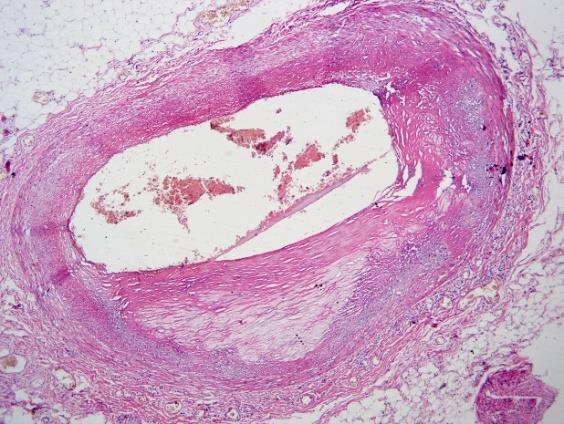

2)冠状动脉粥样硬化(左前降支及左旋支病变Ⅱ级)。

HE,×40 HE,×200

冠状动脉左旋支粥样硬化并钙化